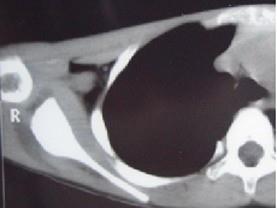

问题 患者,男,34岁,6个月前劳累后出现右肩部疼痛不适,休息后可缓解,曾服用消炎药,对症治疗,效果不佳,实验室检查正常,请结合所提供的图像,选择最佳选项 ( )

选项 A、良性骨母细胞瘤 B、骨样骨瘤 C、骨梅毒 D、骨髓炎 E、右股骨骨纤维异常增殖症

答案 B